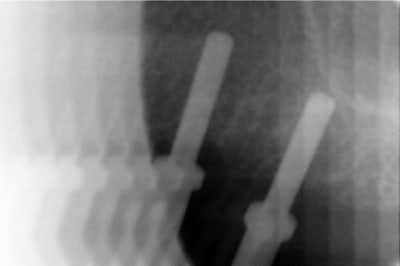

j'effectue demain mon premier Summers

et je suis presque près, à part une question

de dernière minute que je vous soumets en urgence:

comment se répérer sur le forêt pilote pour une profondeur de forage de 4 mm ?

la première graduation est à 7 mm, et les jauges ne se vissent pas si bas

avez-vous un truc ? ( à part l'estimation visuelle )

ci-joint scan pour les curieux

je pensais faire un aplanissement de crête jusqu'à une largeur de 7 mm pour un WP

évidemment, sans aplanissement, on a 7 mm au forêt pilote,

mais par la suite, je perds la distance de travail au fur et à mesure que les diamètres croissent, la distance diminue

( voir scan )

apparement, sur ton image, tu as bel et bien 7 à 8 mm d'os.

donc, tu fores à 7 avec un stop, si tu veux aplanir, tu le fais ensuite.

il me semble que tu as largement la place pour un 8mm et même un 10mm en perforant le sinus avec ou sans summers.